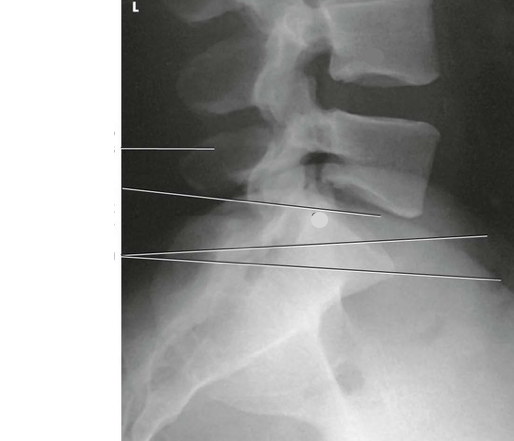

Label the image

7b715ad3-6c1f-467d-8dbc-9bbfbe4881fb (image/png)

Answer

L4

S1

spinous process

intervertebral disk space

iliac crest